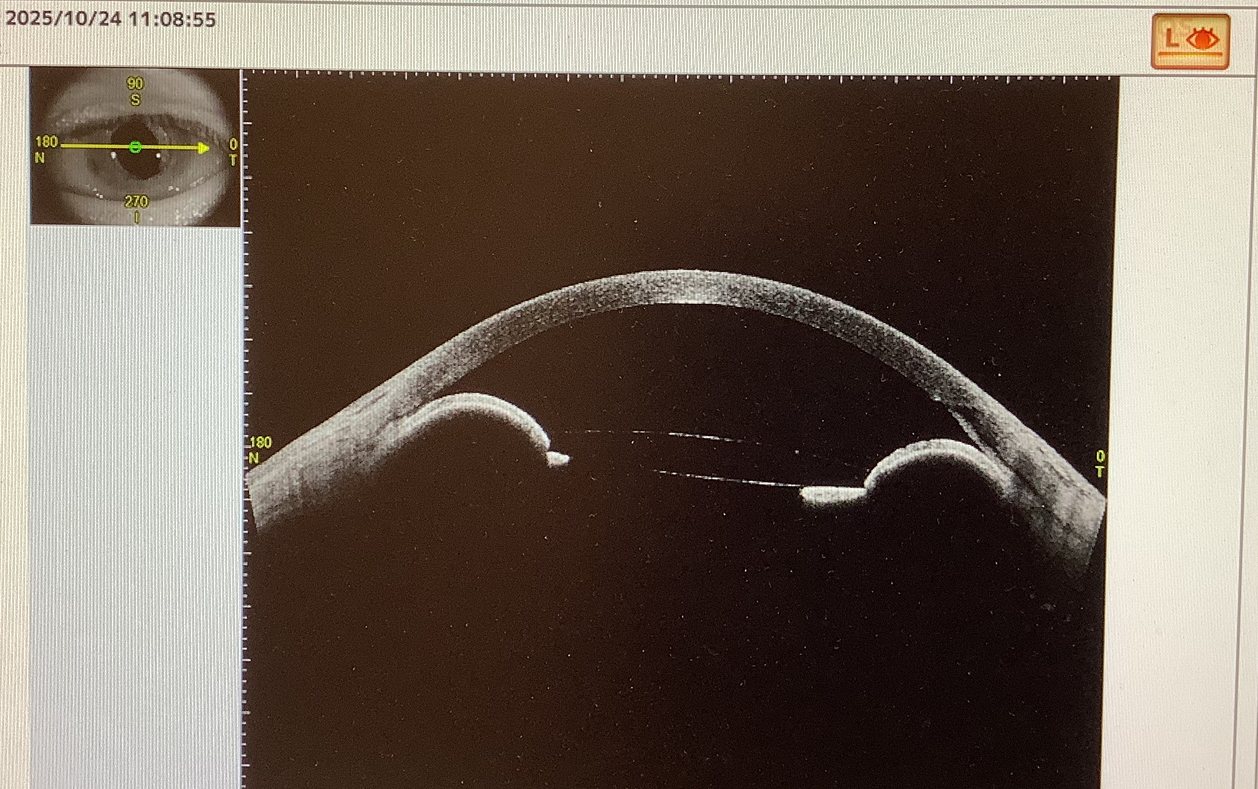

今日の外来では約5年前に両眼とも眼内レンズのズレで、そのズレたレンズを取り出し新たなレンズを眼の壁にレンズを固定する強膜内固定の手術を受けていただいた50歳代半ばの男性が、今朝から『左眼が痛くて、スクリーンがかかった見え方になってしまった』と急遽いらっしゃいました。この方は、時々、レンズの後ろに虹彩が引っかかってしまう“虹彩捕獲”という状態を起こしていたのですが、今回は虹彩が完全にレンズの後ろに回ってしまい瞳孔がレンズで塞がってしまう“逆瞳孔ブロック”という状態を起こしてしまっていました。“逆”というのは、通常の瞳孔ブロックというのは、閉塞隅角緑内障やぶどう膜炎などで虹彩と瞳孔がくっついてしまい眼の中の水の循環ができなくなってしまう状態ですが、この患者さんでは虹彩がレンズの後ろ側に回って起こる瞳孔ブロックなので“逆”がつきます。虹彩より後ろ(硝子体側)にある“毛様体”から眼の中の水(房水)が作られ、瞳孔を通って眼の前のスペース(前房)に回り、角膜と虹彩の付け根の“隅角”から房水は眼の外に流れていくのですが、瞳孔ブロックでも逆瞳孔ブロックでも、瞳孔が閉じてしまうと、房水は作られるのは続いても、瞳孔を通りにくくなり、硝子体の中に水がどんどん溜まり圧が上がることで、隅角が閉じて、余計に房水の排出が悪くなり眼圧がどんどん上がってしまうという悪循環を生じます。

この患者さんも眼圧が60mmHgを超え、眼がパンパンになってしまったため、眼が痛くなり、角膜が浮腫んで見え方も悪い状態となっていました。強膜内固定の手術の時に虹彩切除をしていれば、虹彩の前後で房水の流れができるため、このようなことにはならないのですが、この患者さんでは虹彩切除をしたいなかったので、レーザーで虹彩に穴を開けるレーザー虹彩切開術(LI)を行わないといけないかと思ったのですが、今回は瞳孔を開く点眼薬(散瞳薬)を使うことで、虹彩が眼内レンズの前方に戻り逆瞳孔ブロックが解除されたので、今日のところはレーザーの処置はせずに後日改めて行うこととさせていただきました。強膜内固定の時に虹彩切除をするかどうかは議論のあるところかとは思いますが、このようなケースを経験すると、しておいた方がよいかと思いました。